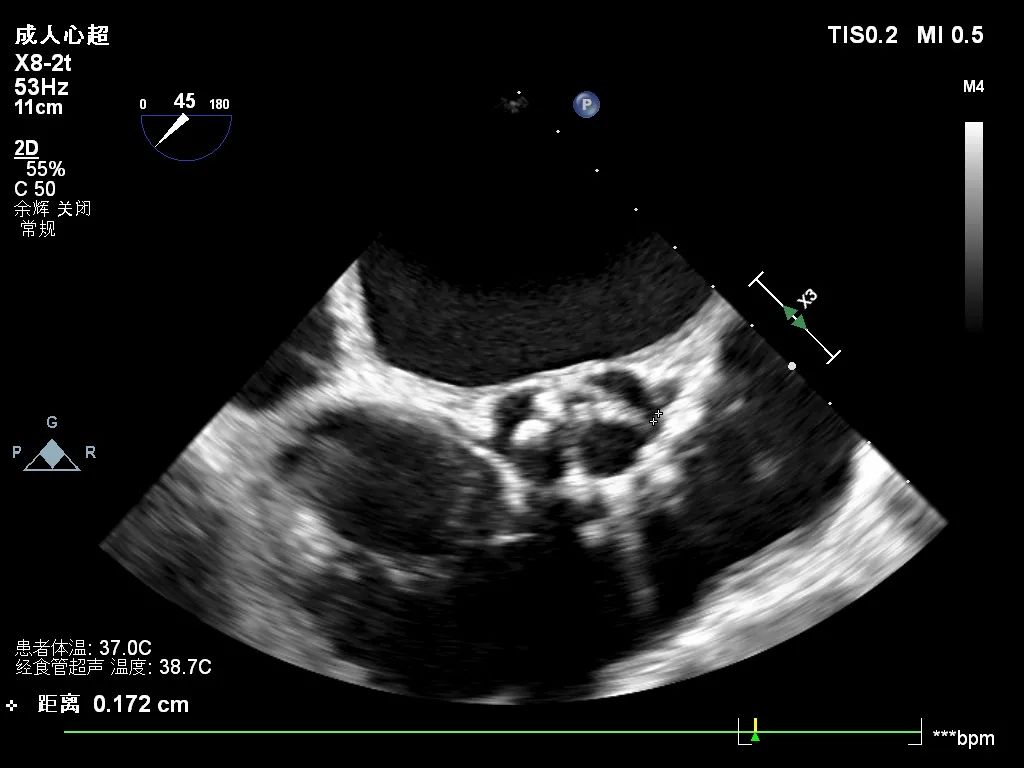

心脏超声

峰值流速:4.3M/s; 最高跨瓣压差:73mmHg; 平均跨瓣压差:43mmHg; 左室射血分数EF值:0.59; 左室舒张末期内径(LVD):5.3 cm。

主动脉瓣评估:三叶瓣,不均匀钙化,右无窦钙化交界处钙化严重,左冠瓣无明显钙化,瓣叶较厚,右无钙化明显。主动脉重度狭窄并中度关闭不全,二尖瓣轻中度狭窄,左房扩大,同时二尖瓣三尖瓣都伴有返流。

术前超声影像

术中球扩后超声影像

术后超声影像